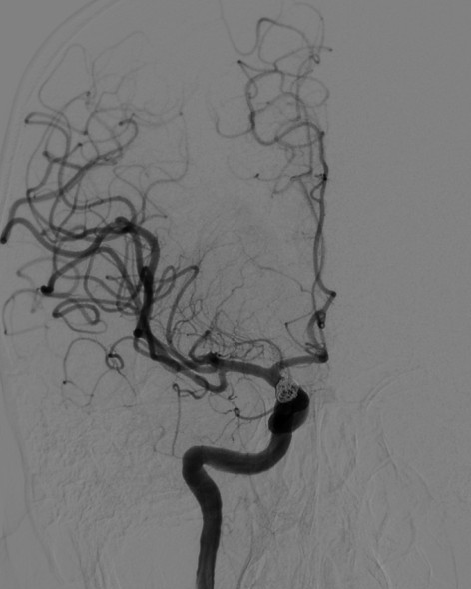

术前DSA造影:动脉瘤大小:4.9mm*4.8mm,动脉瘤颈:4.0mm;载瘤动脉远端直径:2.4mm,近端直径:4.0mm,长度:19.9mm。

DSA正位造影

动脉长鞘怎么置入深谋远路 | 千人皆翘首,万唤今始来——国内首款7F长鞘在血流导向密网支架联合弹簧圈栓塞治疗动脉瘤的首次应用_https://www.jmylbn.com_新闻资讯_第21张

DSA侧位造影